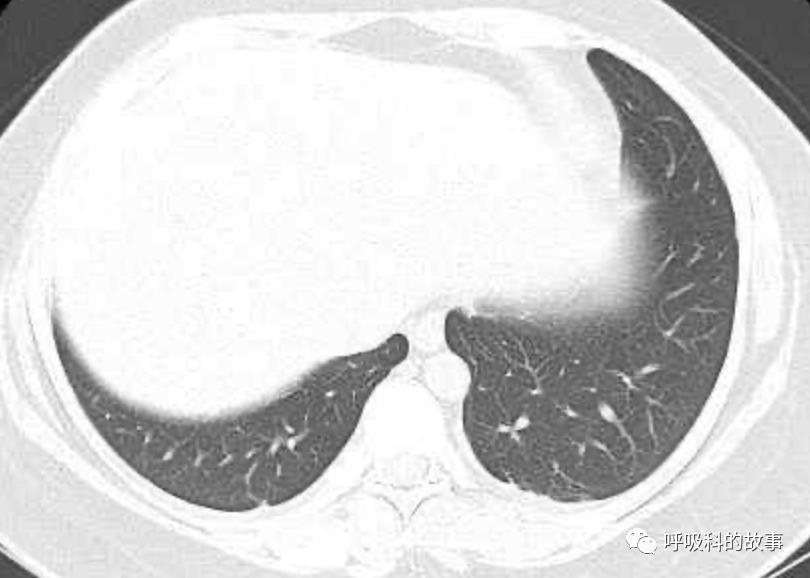

可是在6月26日(往院第18天)仍持续发热的情况下复查肺部CT,肺部病灶已明显吸收了。那么患者发热的原因到底是什么呢?为什么患者高热的情况下血白细胞不升反降,C反应蛋白也没有明显增高?这个时候消化科医生也迷茫了,这可怎么办?于是请感染科和呼吸科医生一起会诊,共商计策。